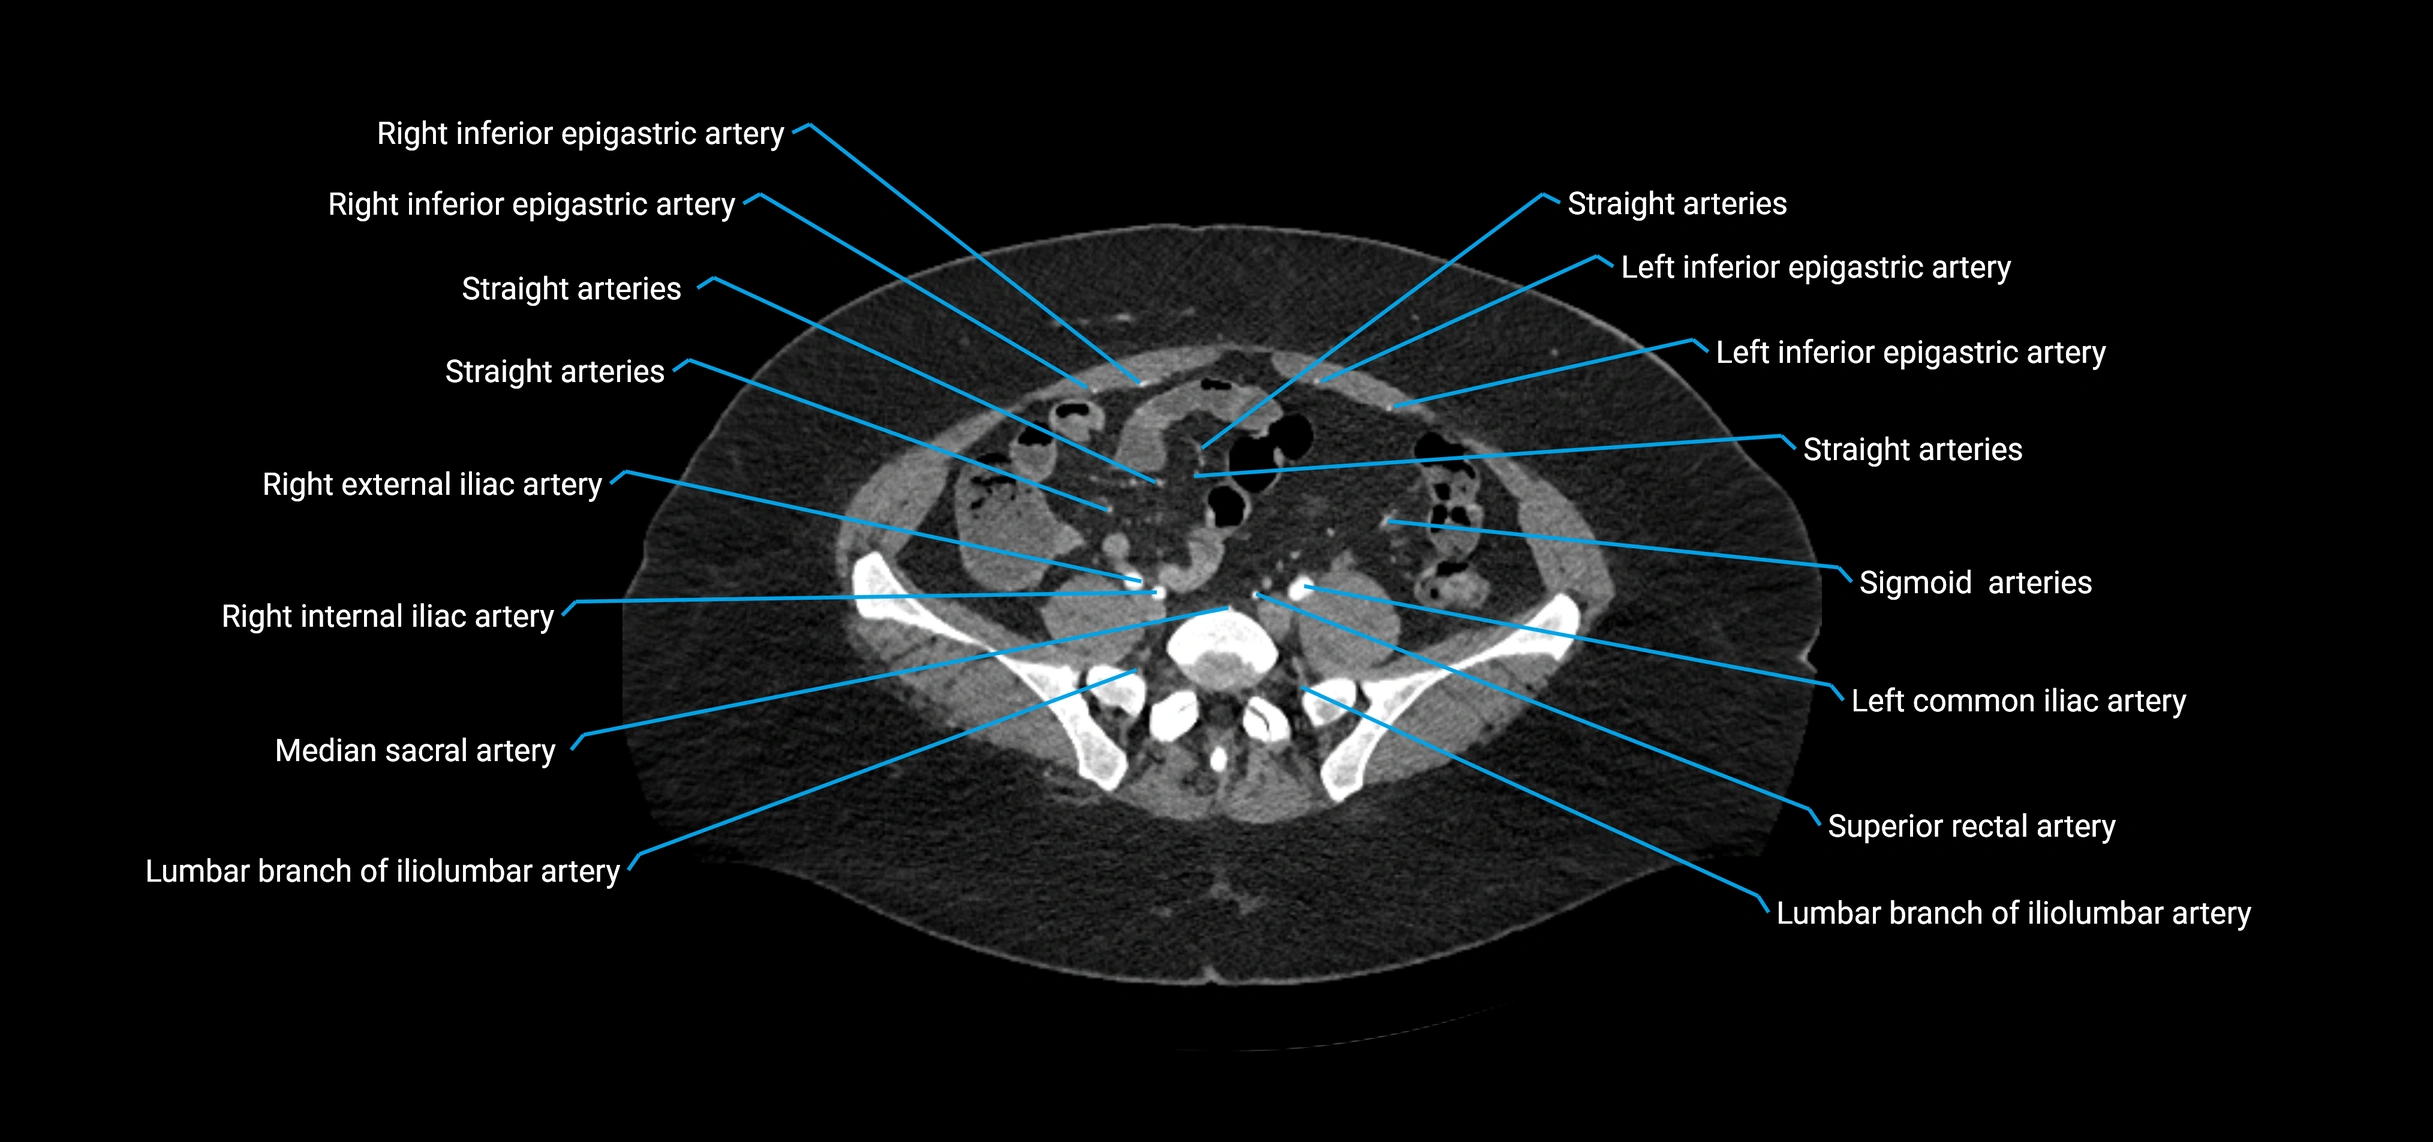

CT images

image

Contrast-enhanced CT (CTA):

• Gold standard for abdominal aortic imaging

• Provides excellent detail of lumen, wall, aneurysm, thrombus, and branch vessels

• Multiplanar and 3D reconstructions help in aneurysm measurement, stent graft planning, and dissection evaluation